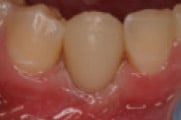

Initial situation

Recurrent decay on the distal surface of tooth No. 20. Due to the fractured buccal cusp and weak unsupported lingual cusp, tooth No. 20 required full crown restoration. The existing crown was removed and an interim temporary restoration was placed using 3M™ ESPE™ Protemp™ Crown Temporization Material, to be followed by a permanent PFM crown.